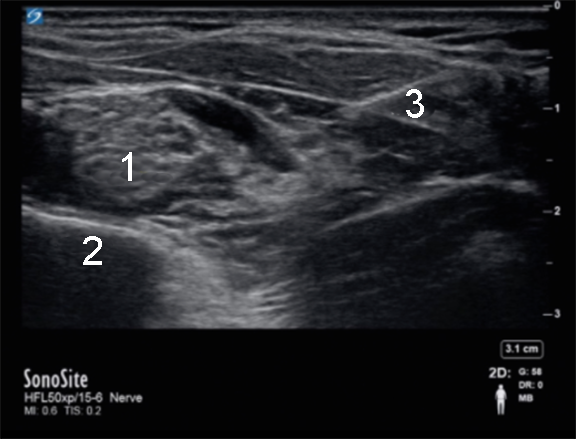

Supraclavicular Nerve Block Post Injection Image

Brachial Plexus

Pleura

Needle